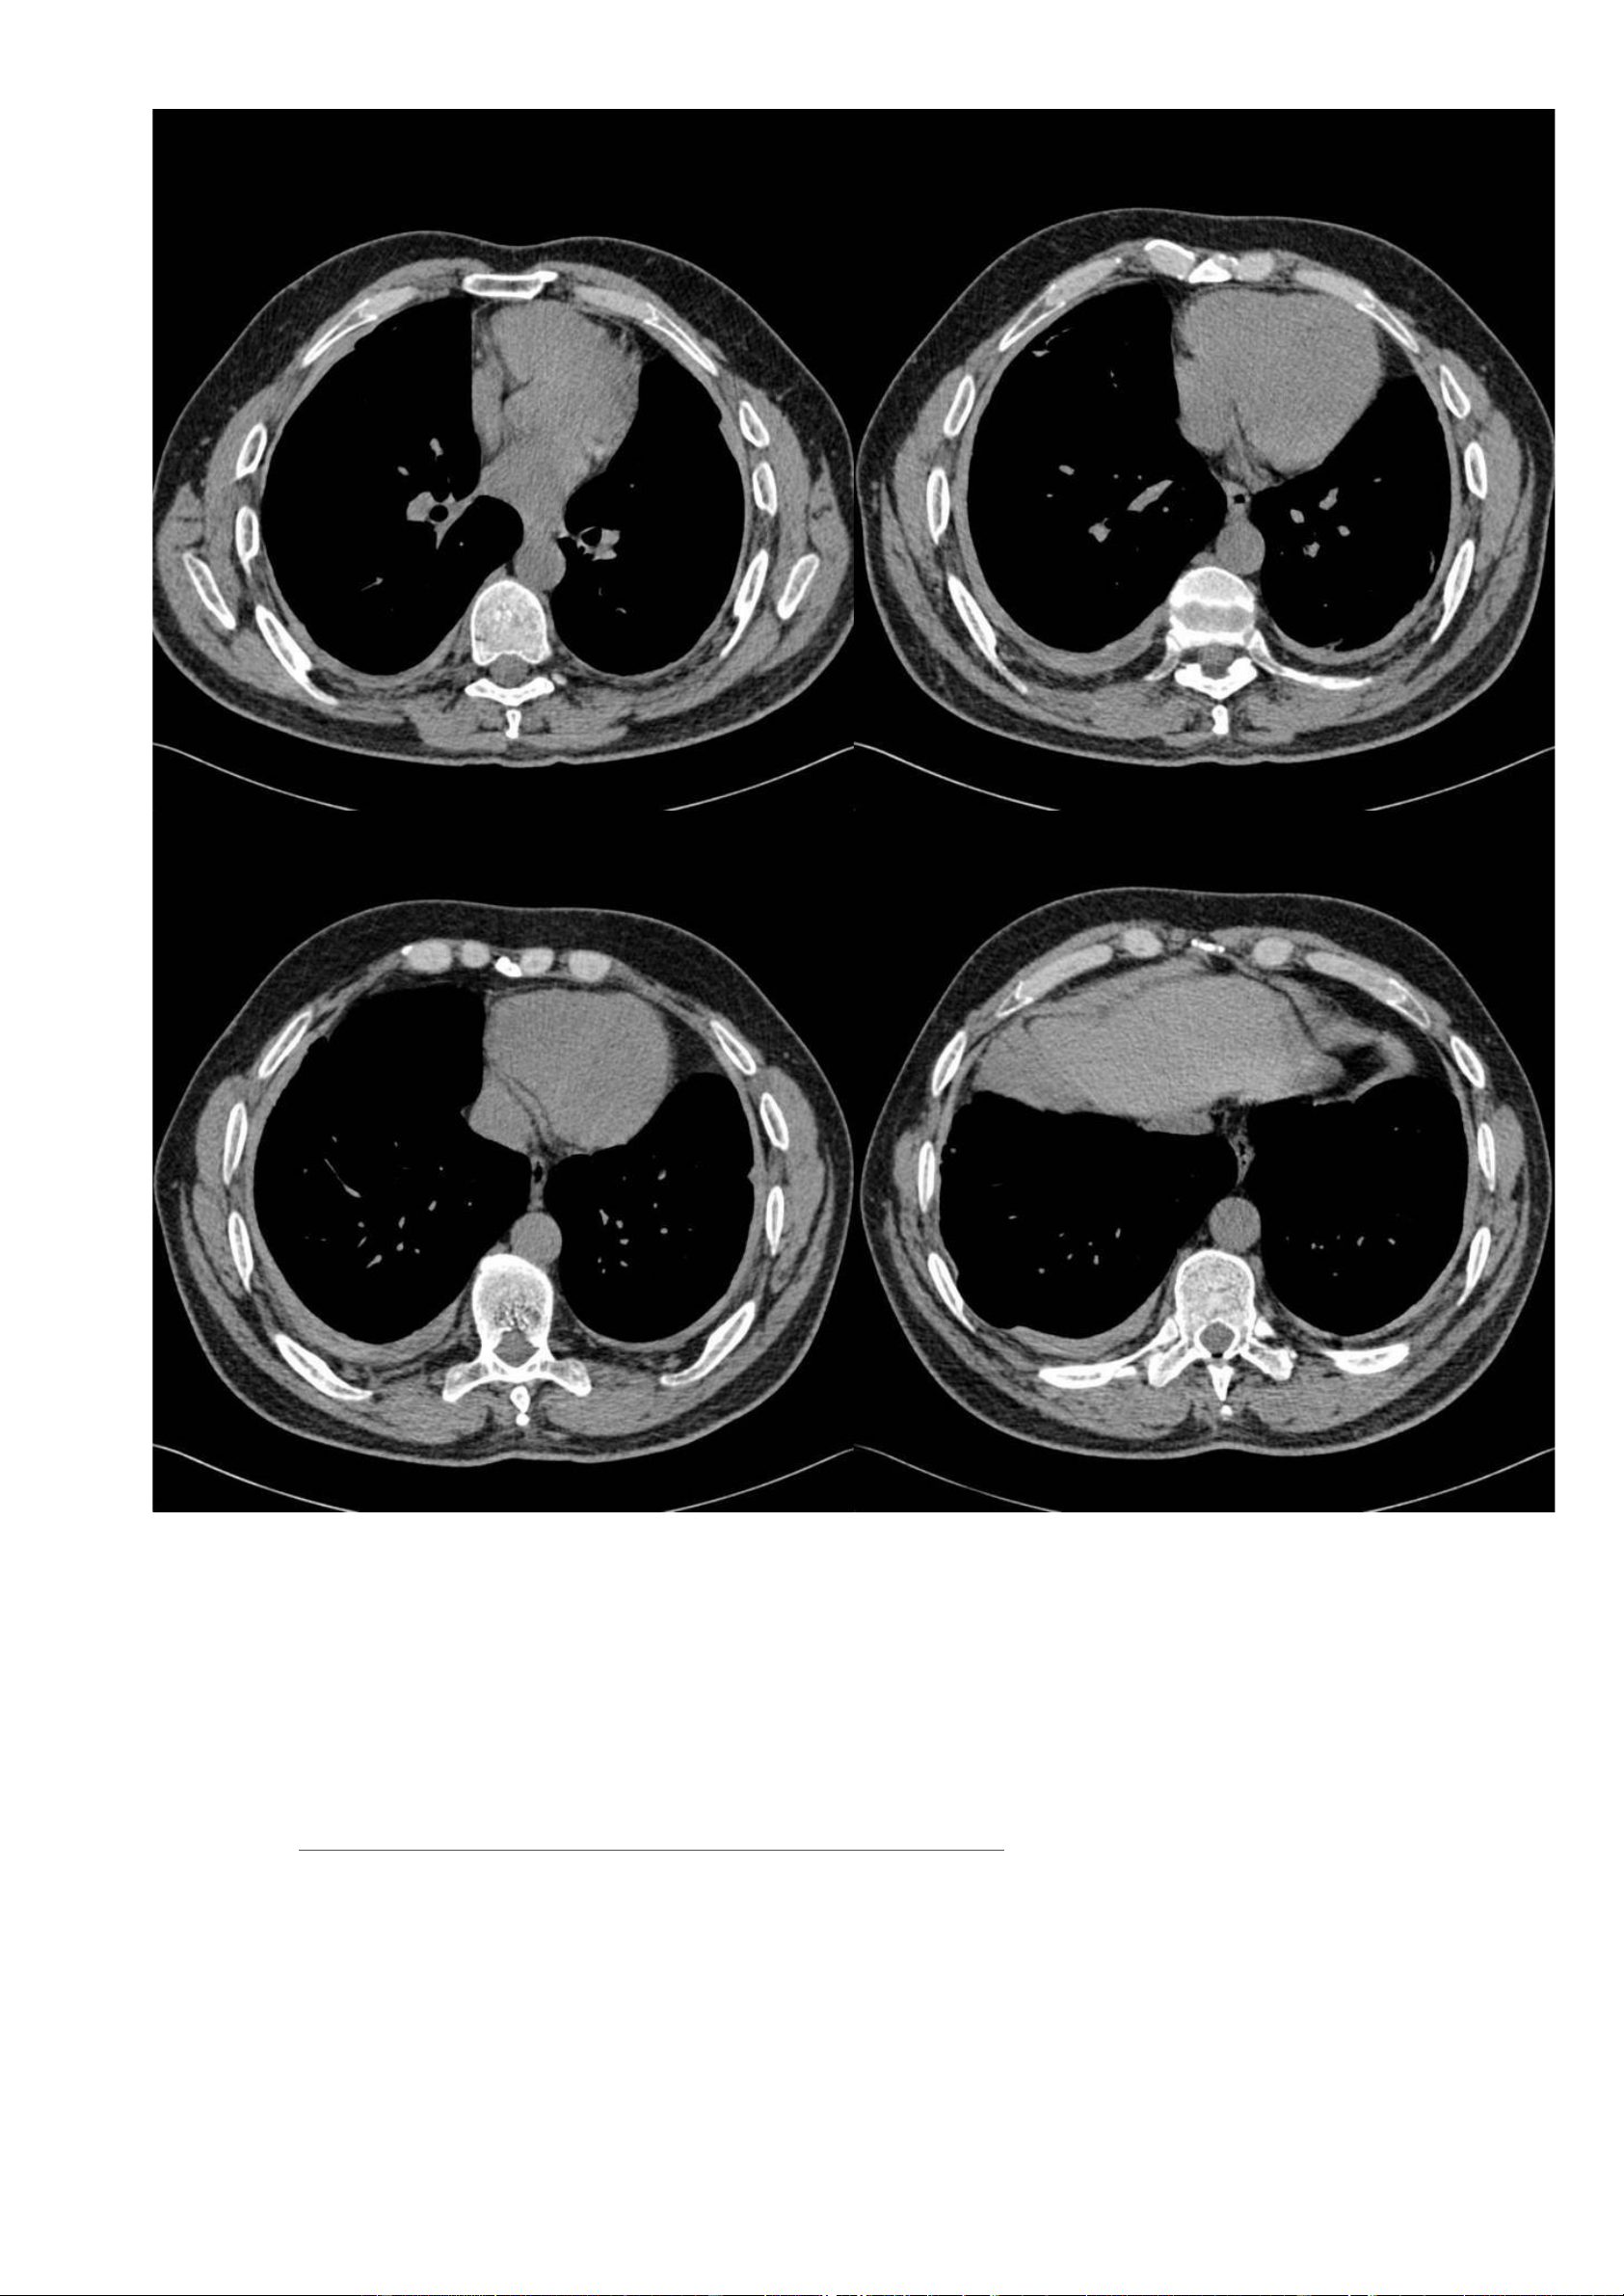

+ Cửa sổ trung thất – không tiêm thuốc cản quang: lOMoAR cPSD| 22014077 Phan Tùng Bách

▪ Ghi nhận các mảng màng phổi hai bên.

▪ Không có tràn dịch màng phổi (pleural effusion), không có hạch to. -

Các dấu hiệu trên cửa sổ nhu mô và cửa sổ trung thất, phù hợp với bệnh phổi-màng phổi liên quan đến amiăng. 7.3. Trường hợp 3: -